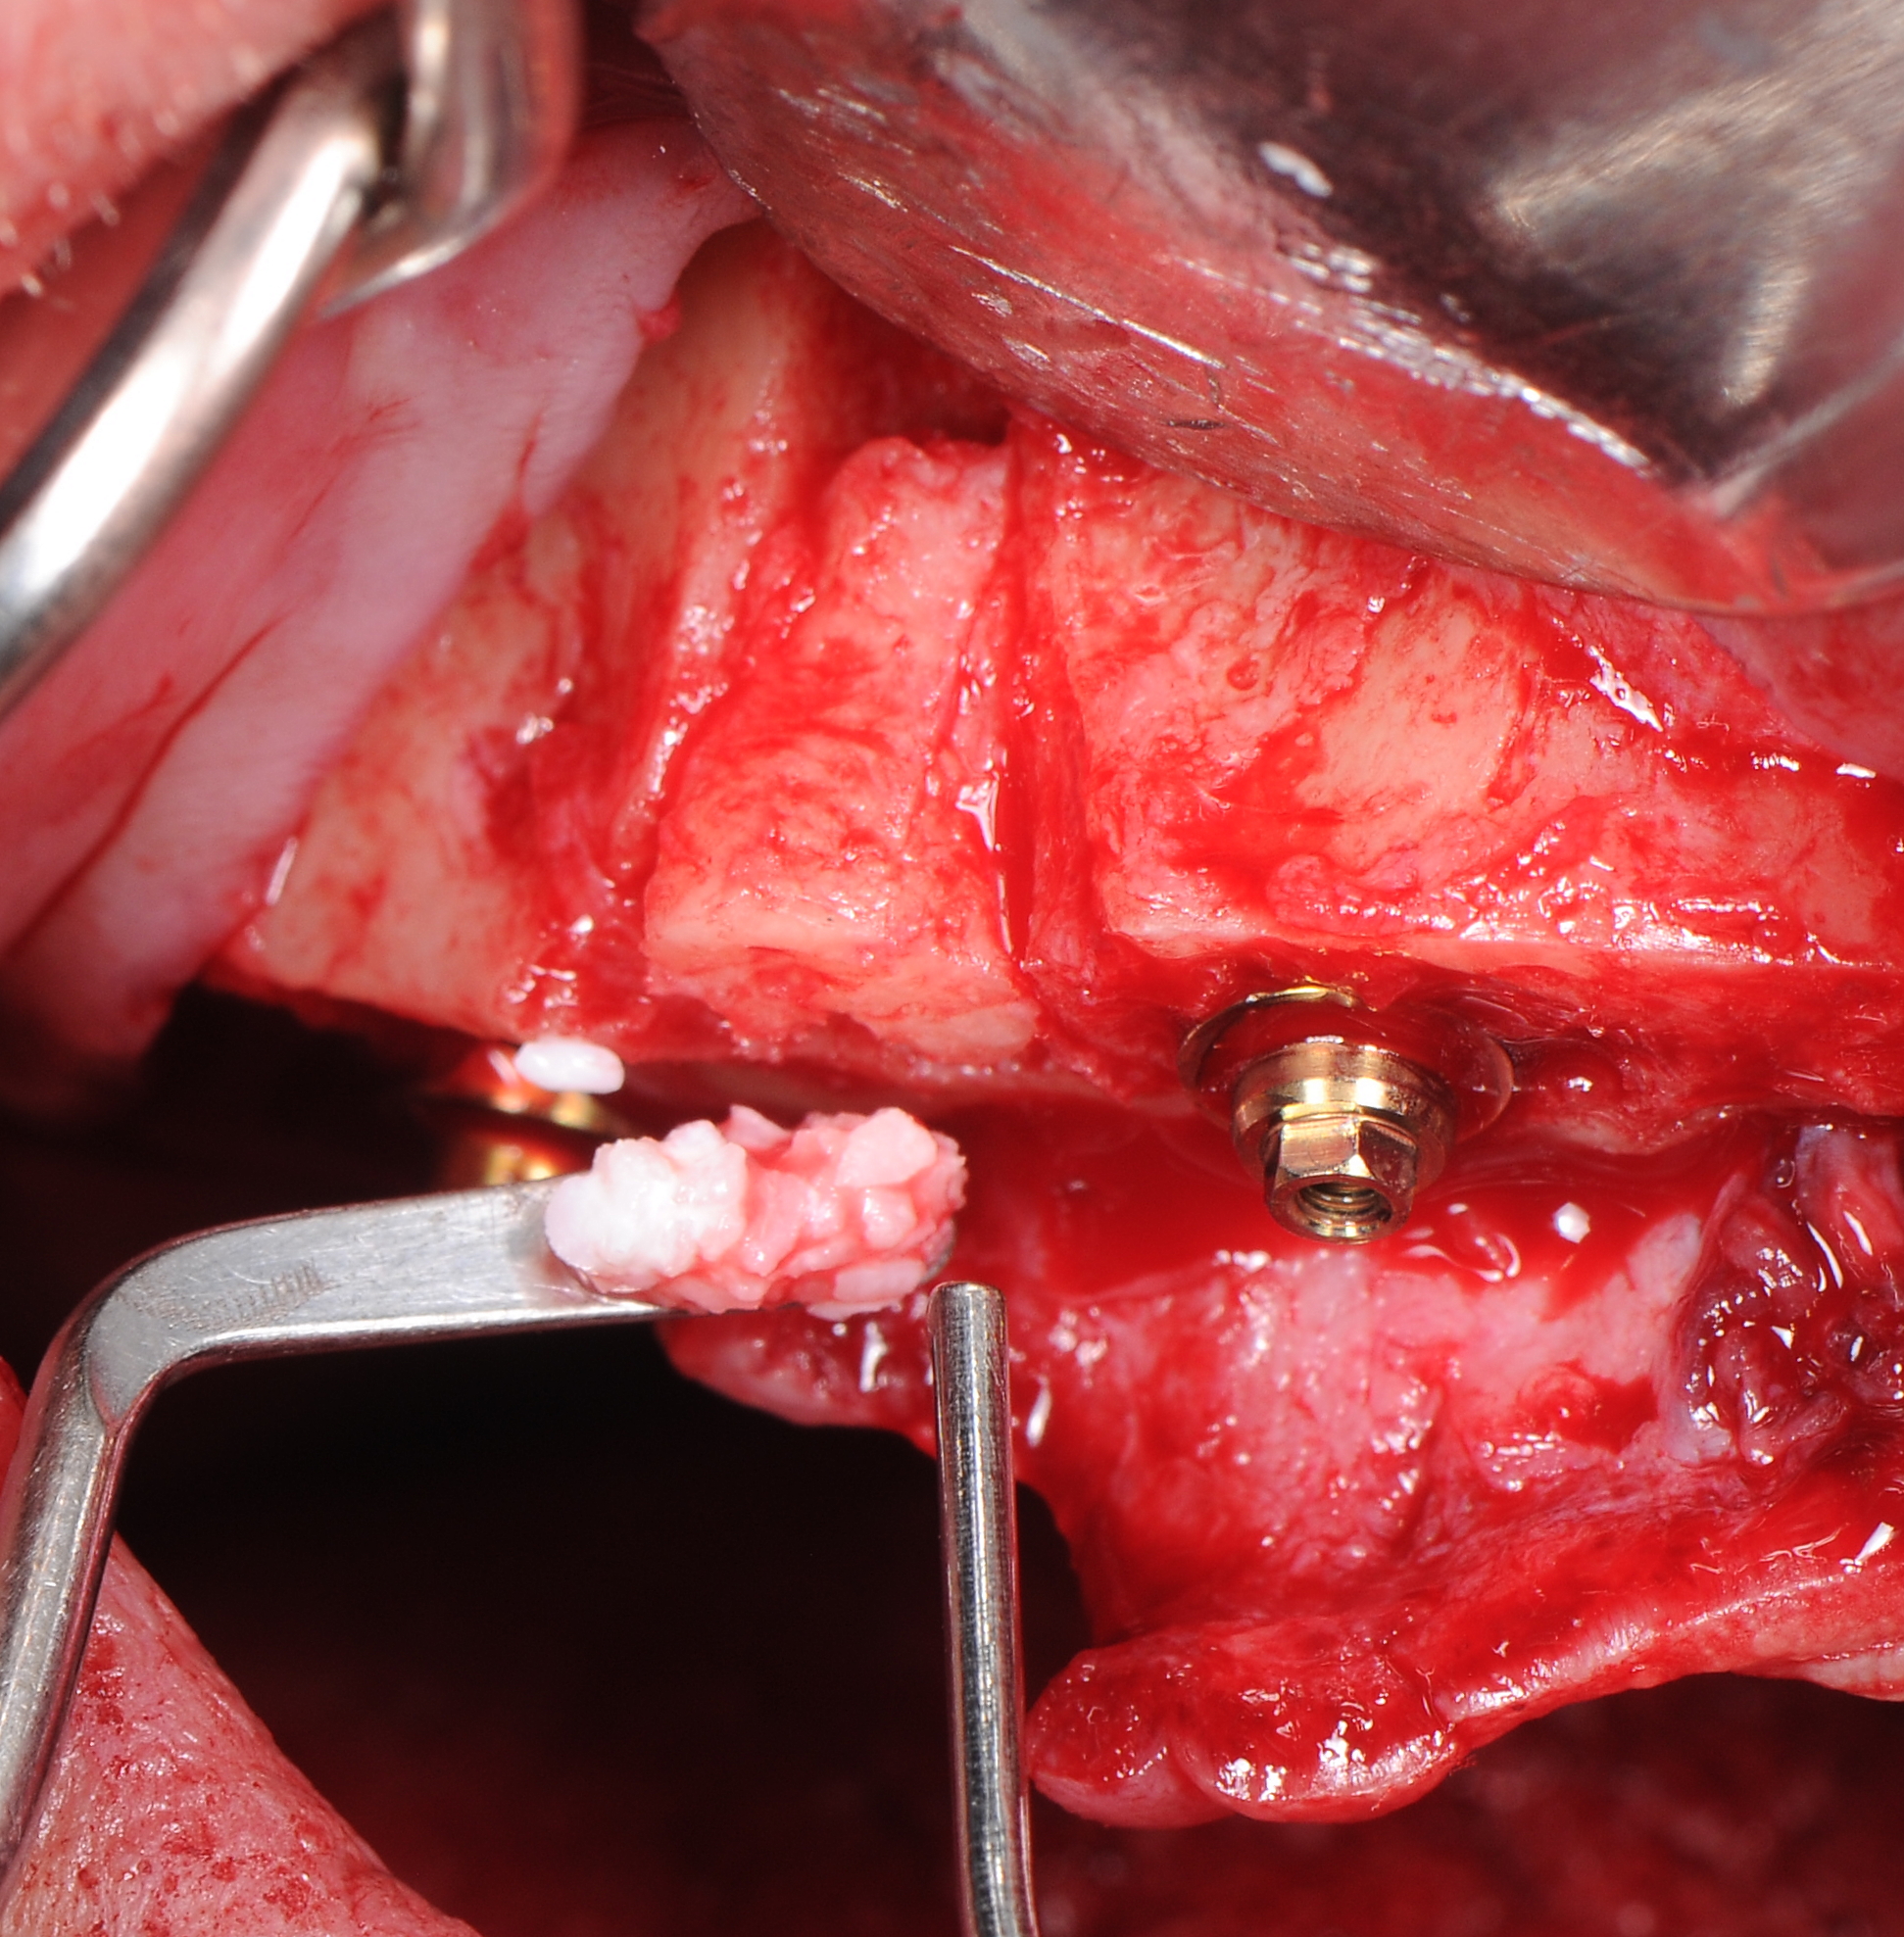

Лунка удаленного 1.3 зуба аугментирована костным фрагментом полученном при редукции альвеолярного гребня. Его клиновидная форма позволила провести фиксацию в лунке без использования дополнительных материалов: титановых винтов или пластин. Поднутрения в окружности костного фрагмента были заполнены костно-пластическим материалом «OsteoBiol ® mp3». Области «Multi – unit» абатментов и зоны костной аугментации дополнительно изолированы коллагеновыми мембранами Creos Xenoprotect. (рис. 22-25).